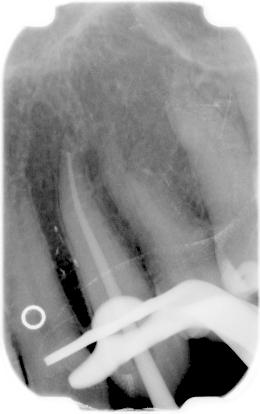

Met een elektronische lengtebepaler wordt vastgesteld hoeveel millimeter de lengte van een gebitselement is. Op het occlusale vlak wordt een punt genomen (bijvoorbeeld de mesiobuccale knobbel van de bovenmolaar) ten opzichte waarvan de lengte wordt bepaald tot aan de apex.

Een vijl die in het apicale gebied goed contact heeft met de kanaalwand wordt langzaam richting apex geduwd. Op het moment dat de punt van de vijl het periapicale gebied bereikt geeft de lengtebepaler een signaal dat aangeeft dat de apex bereikt is. Dit is het enige betrouwbare meetpunt. Deze lengte wordt gemeten. De metingen die aangeven dat men nog enkele millimeters van de apex verwijderd is, zijn relatieve metingen en derhalve minder betrouwbaar dan de apex meting. Vervolgens wordt bepaald hoeveel millimeter vanaf de apex het einde van de kanaalpreparatie moet komen.

• De lengtefoto is vaak alleen een bevestiging van de bepaalde lengte en de vijlen zijn nooit voorbij de apex.

• Een lengtefoto is altijd nodig om krommingen of foutmeldingen te constateren.